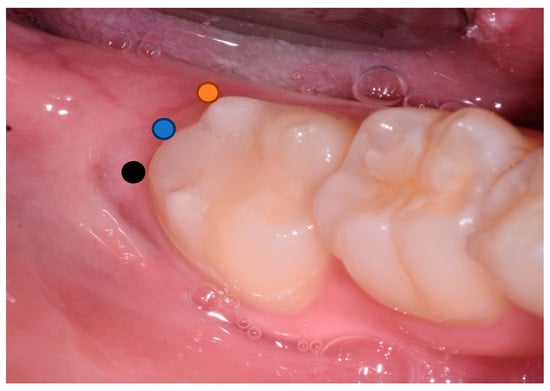

- Probing depth was measured 3 and 6 months after surgery at the DV, DM and DL points on the distal aspect of the second molar as shown in Figure 3.